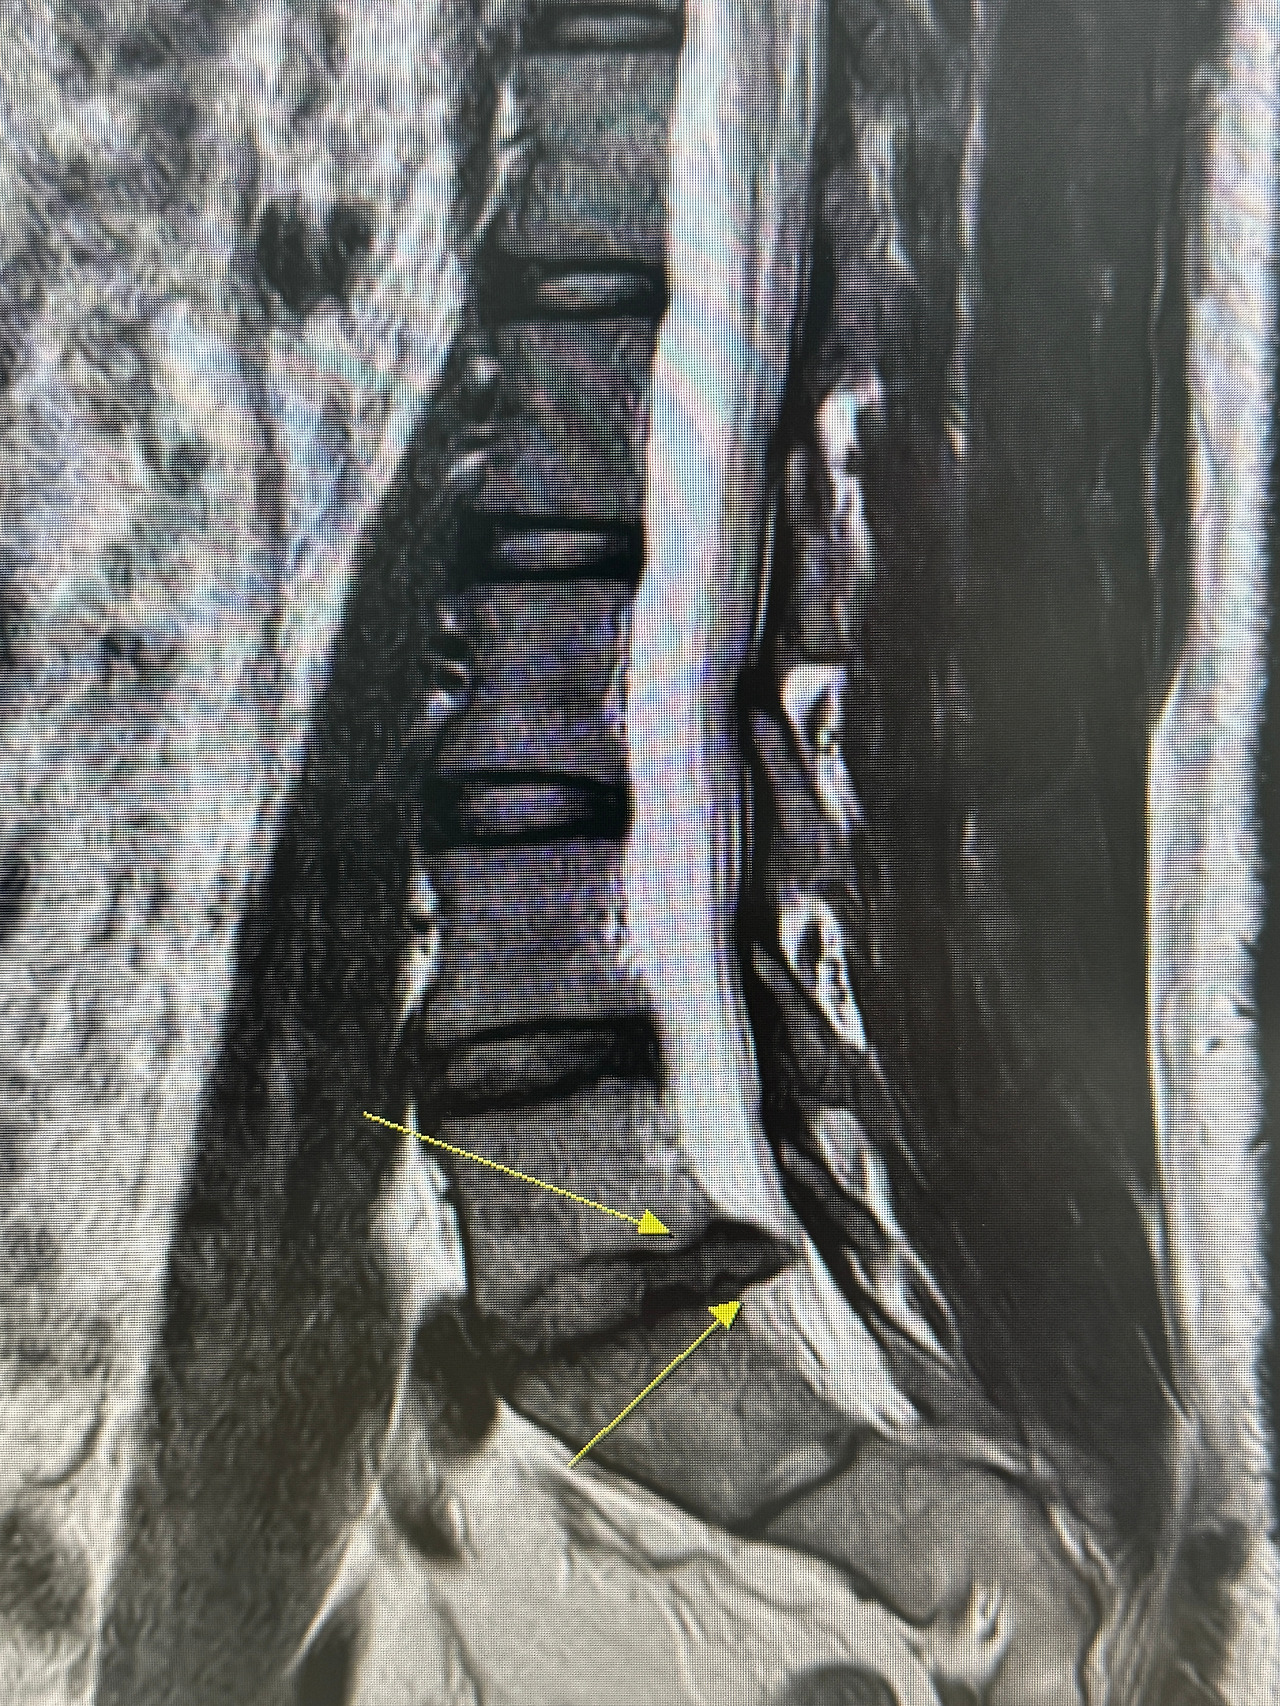

2022년 마지막으로 세계일주를 간다는 글을 쓰고 벌써 2년 넘는 시간이 흘렀다. 그 사이 세계 일주에 대한 갈망이 사라진건 아니지만 여러 가지 이유로 하염없이 미뤄졌었다. 그 중 가장 큰 이유는 갑작스럽게 생긴 허리디스크 때문이였다. 어느 날 갑자기 일어날 수 없을 정도의 고통이 생겼고 아니나다를까 검사를 해보니 디스크가 터진 상태였다. 가만히 앉아있을 수가 없을 정도로 고통이 심해서 세계일주는 물건너 가나 생각했다.

못하게 하면 사람이 더 하고 싶어지는 법. 허리 디스크가 생겼지만 오히려 세계일주에 대한 열망은 더 커졌다. 이대로 포기하면 평생 출발할 수 없을 것만 같아 스스로에게 1년의 유예기간을 선고하고 그 사이 회복을 하기로 했다. 그리고 1년 후 나의 상태가 어떻든지 일단 출발하기로 마음 먹었다. 다행히 그 사이에 허리가 조금 회복을 했다. 여전히 오래 앉아있거나 조금 무리를 하면 오른쪽 다리가 저리고 엉덩이가 뻐근해오지만 그래도 약간의 운동을 할 정도는 되었다. 스스로 정한 유예 기간에 맞춰서 몸이 회복을 하는가 싶다.

KakaoTalk_20250316_124812992.jpg 허리 MRI를 볼 줄 모르는 사람이라도 디스크가 얼마나 심했는지를 알 수 있다.